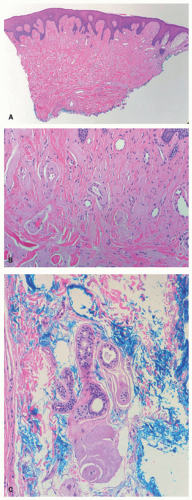

A hoarse or weak cry is the first identifiable feature of the disease, typically manifesting at birth or within the first few years, and progressively worsening throughout an individual’s life. The cutaneous features of the disease vary with age. Infants and young children typically develop vesicles or bullae with hemorrhagic crusting on the face and upper extremities and within the mouth—often secondary to trauma. These lesions heal with varioliform scarring (Figure 10-1A).

Later in childhood, there is an increase in hyaline deposition within the dermis leading to the development of yellow papules and plaques on the face, eyelids, neck, and hands. The scalp can also be affected, resulting in patchy or diffuse hair loss. Thick, waxy yellow plaques favor flexural surfaces, whereas verrucous plaques favor extensor surfaces. In about 50% of individuals, a string of bead-like papules appears on the free eyelid margins, often leading to a loss of lashes (Figure 10-1B and C). Involvement of the eyelid margin may be complicated by corneal ulcers. A cobblestone appearance may appear on mucosal surfaces within the mouth.

There is deposition of pale, eosinophilic, amorphous material surrounding small capillaries and eccrine ducts in the superficial dermis. In more developed lesions, deposits undergo hyaline thickening with an “onion-skin” appearance. Sweat glands are damaged with increased hyaline deposition (Figure 10-2). Hyperkeratosis and papillomatous may be seen.6 The hyaline deposits are periodic acid-Schiff (PAS) positive and diastase resistant, and stain with Alcian blue as well as Sudan black on frozen sections.7

Histopathologically, there is significant overlap with erythropoietic protoporphyria (EPP) (Figure 10-3). However, these can be differentiated by the deeper, more extensive involvement of hyalinization in LP, and clinically by the distribution in more sun-exposed areas in EPP. Colloid milium and amyloidosis may be considered, but like EPP, are also typically more superficial.